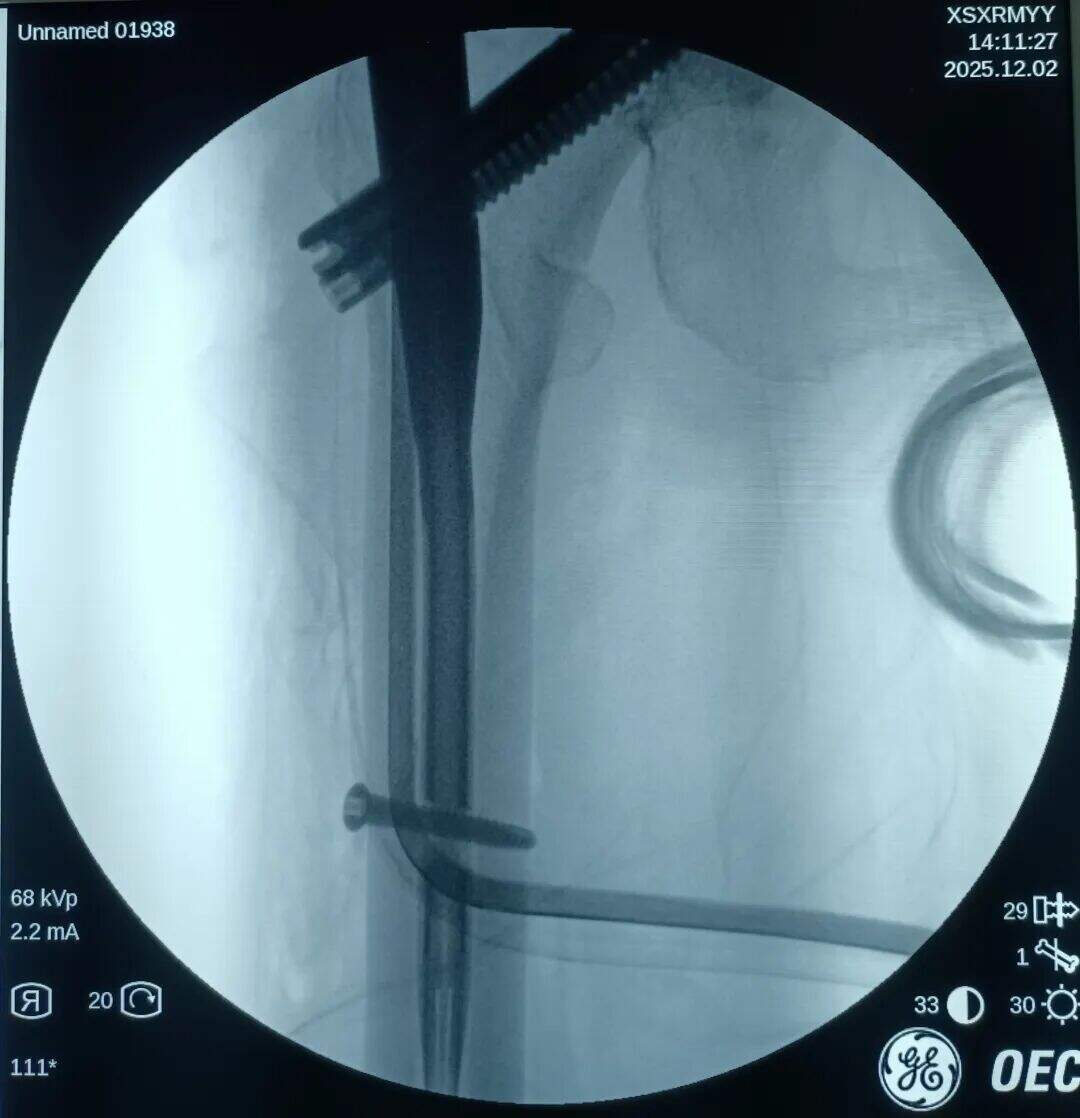

Narezen je bil 2 cm prednji mini-rez. Mesto zloma je bilo opazovano z prstom. Ugotovljeno je bilo, da je proksimalni fragment premaknjen navzgor, distalni fragment pa nazaj in zaklenjen. V mesto zloma je bil vstavljen klešča; pod vodstvom prsta v kombinaciji s kleščo so bili zaklenjeni fragmenti odklenjeni. Nato je bila klešča uporabljena za ohranitev kakovosti redukcije z medialno in lateralno kompresijo. Izvedena je bila običajna lokalizacija, vstavitev vodilne žice ter standardni kirurški postopek.

Medularni kanal je bil ozek. Nobenega razširjanja ni bilo izvedeno. Intramedularni klin s premerom 9 mm je bil vstavljen v tesen fit. Prilagoditev anteversije cefalomedularnega vijaka se je izkazala za težko.